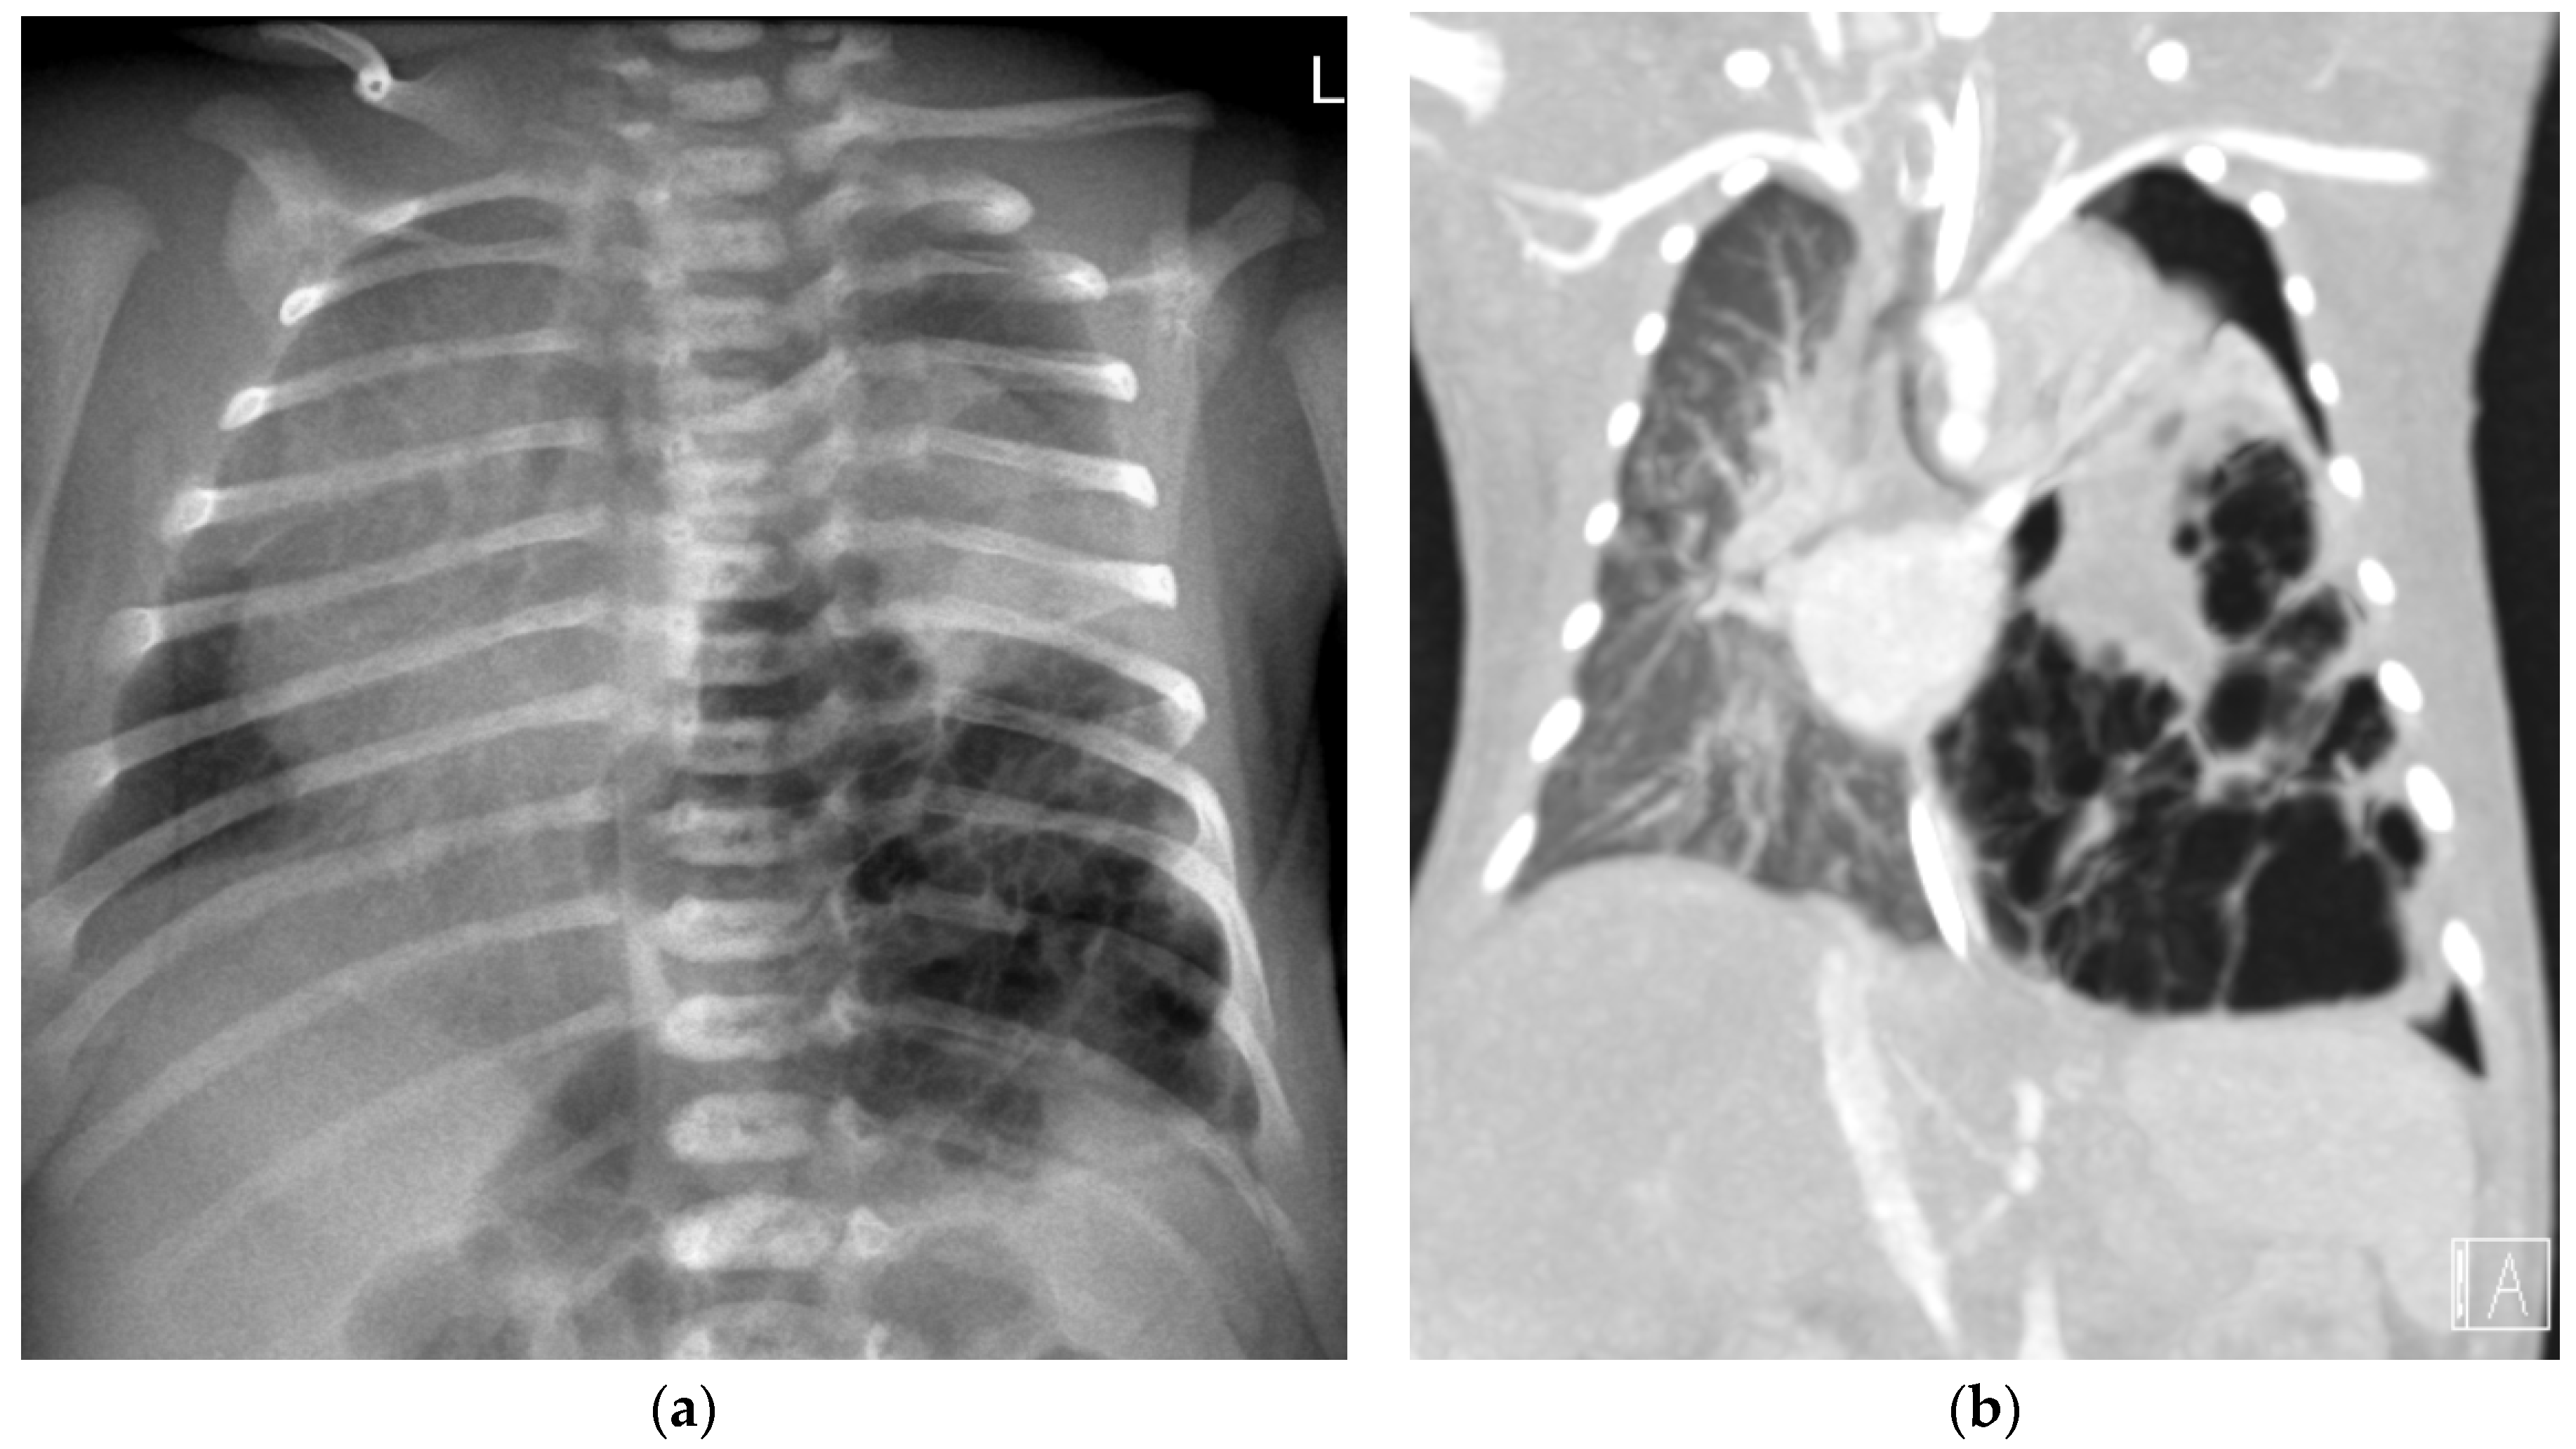

A 6-day-old term girl presented with severe respiratory distress and a large pneumothorax on the right side, requiring chest drainage and a prolonged course of treatment, including intubation (Figure 1a). Chest computed tomography (CT) showed a pneumothorax and a cystic mass on the right upper lobe (Figure 1b). Although lobectomy was recommended, she underwent segmentectomy on day 11 of life. The pathologic diagnosis was CPAM type 4. Due to the early pneumothorax and normal prenatal ultrasound, pleuropulmonary blastoma was suspected. Genetic counseling revealed DICER1 germline mutation. We consulted the IPPBR, and they revised the pathologic specimen. Based on the cellularity and hyperchromasia of spindle cells within the cyst walls, a diagnosis of type I PPB was confirmed (Figure 2). Completion lobectomy, chemotherapy or close follow-up were suggested as treatment options. The parents chose a follow-up regimen. Nine months later, a new bullous lesion (6 mm) appeared in the right upper lobe (RUL) (Figure 1c). Consequently, a completion RUL lobectomy was performed. The patient received no chemotherapy. Currently she is under close monitoring in our pediatric pulmonology and haemato-oncology units, with the periodic evaluations of a DICER1-positive patient, including chest CT scans. She is now 5-year PPB-event free, and thriving.

A 2-day-old term girl presented with severe respiratory distress. Chest X-ray showed large multicystic lesion on the left hemithorax with compressive atelectasis of the lung, small pneumothorax and mediastinal shift to the right (Figure 3a). Prenatal follow-up was normal. An urgent thoracoscopy and positioning of chest tube was performed, followed by CT angiography (CTA) that better delineated the same findings, suggestive of type 1 PPB (Figure 3b). Under left thoracotomy she underwent left lower-lobe lobectomy with complete resection of the mass. The pathologic diagnosis was type 1 PPB, positive DICER1 in the specimen (using PCR amplification with full exonic coverage, followed by NGS sequencing), but negative DICER1 germline. More than a year later, she is well.

Figure 3. Two-day-old infant with respiratory distress. (a) Chest X-ray and (b) Coronal image of CTA: Large multilocular cystic lesion in the right lower hemithorax, with mediastinal shift to the right. There is an atelectasis of the left upper lung and apical pneumothorax.